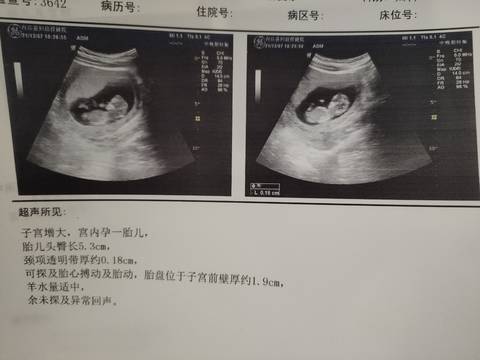

nt过了,能看出是女孩还是男孩吗?

journal_insert_pic_1675520156